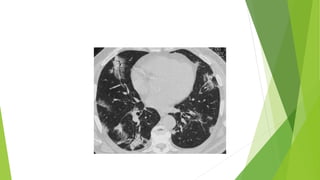

Tomografía computarizada  Esmucho más fácil de ver en TC y su presencia permite asegurar que la lesión es intrapulmonar  Bronquios periféricos visibles en la mayor parte del campo pulmonar